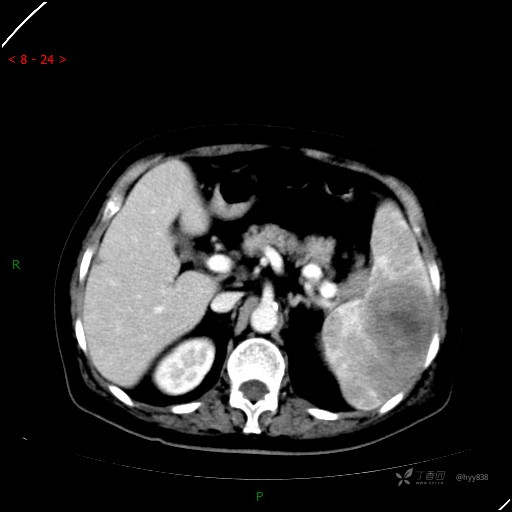

上腹部CT平扫

静脉期